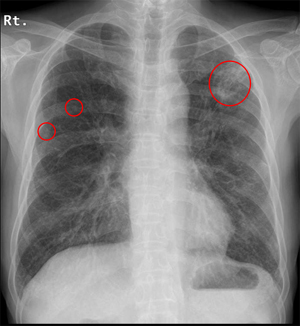

両肺に数少ないが多発結節(小葉との関係は判断困難)の出現、出現速度は速く、増大経過(LVFX抵抗性)

2010.05.27 抗生剤( LVFX )投与開始後 解熱なし

2010.06.2) 初診から5週後

増大したものの一部に空洞形成、左上区の最大のものの空洞内には同心円状・索状構造がみられる